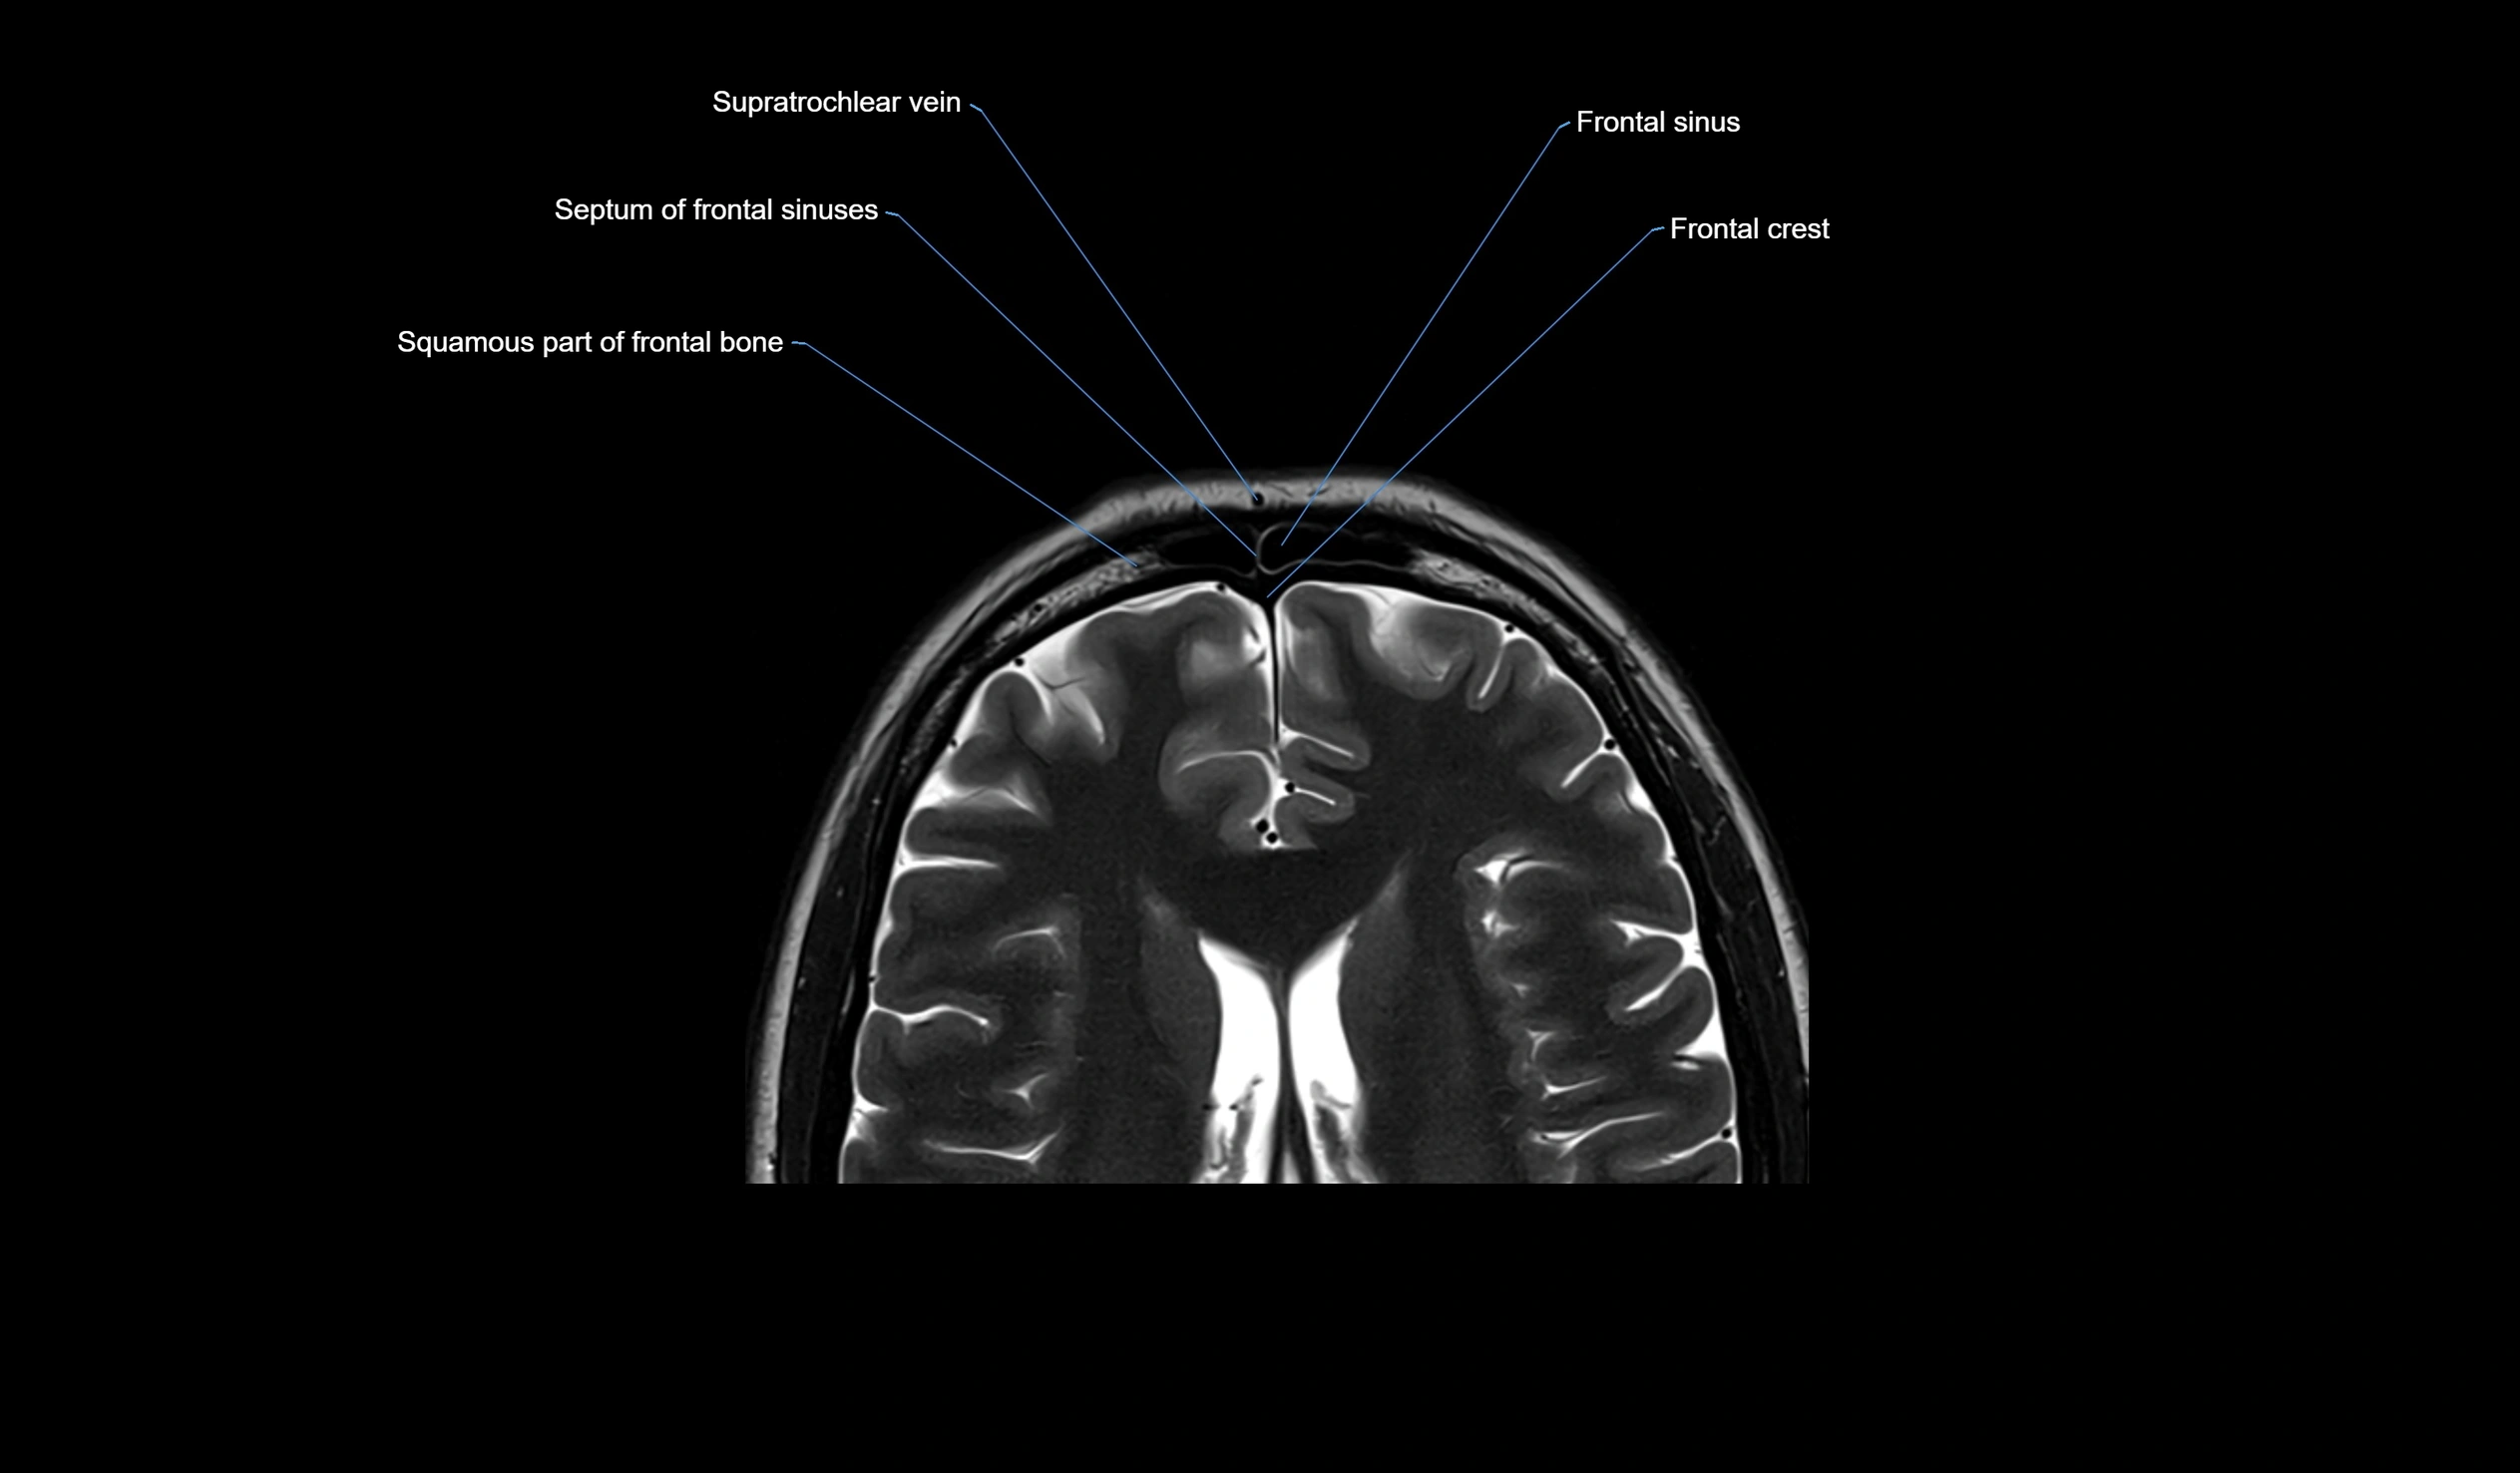

MRI images